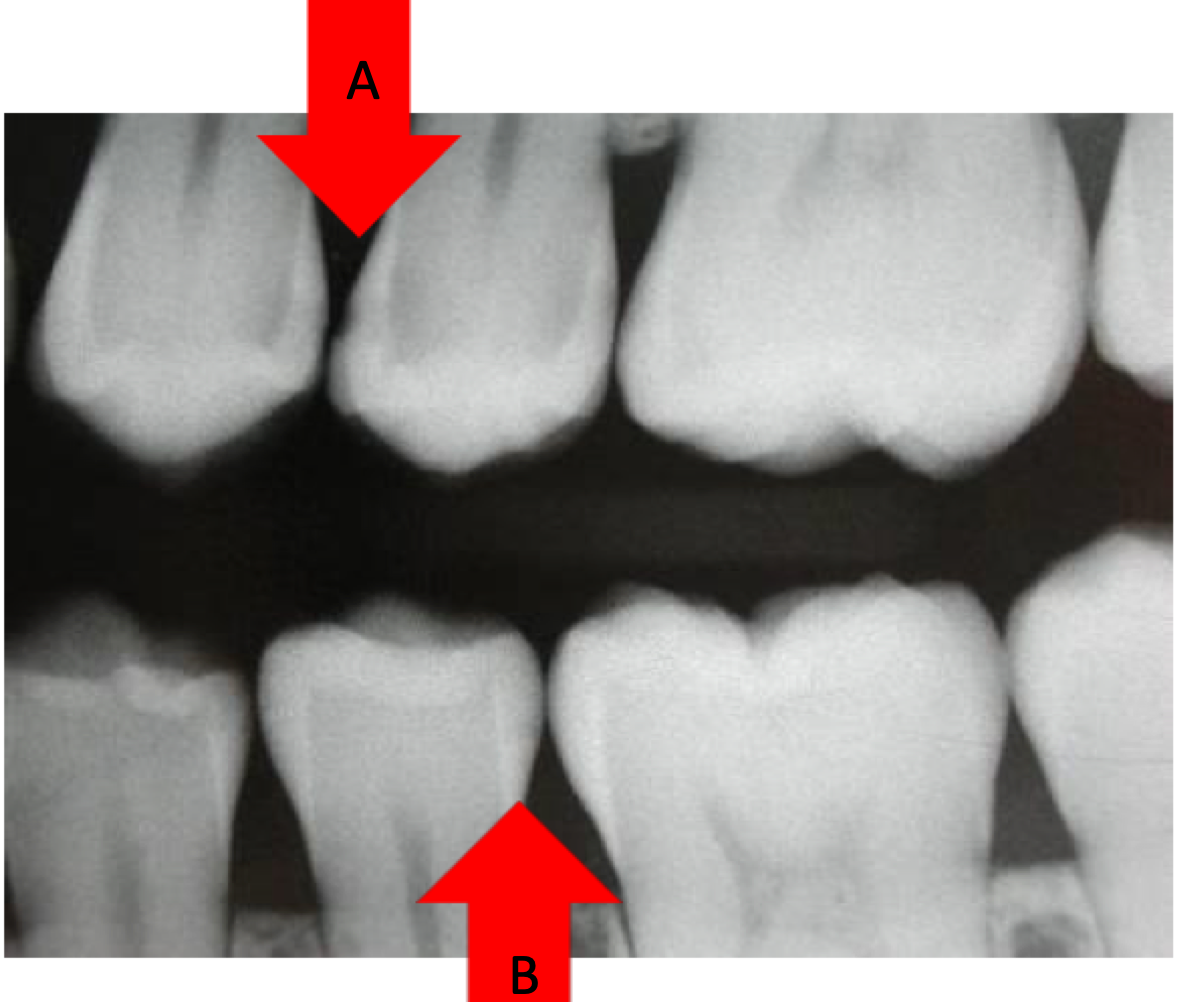

Compare the decalcification in area A and area B?

In area A the tooth surface has been broken. To treat this we will have to cut out the lesion

In Area B the tooth surface has not been broken. We can use preventative measures.